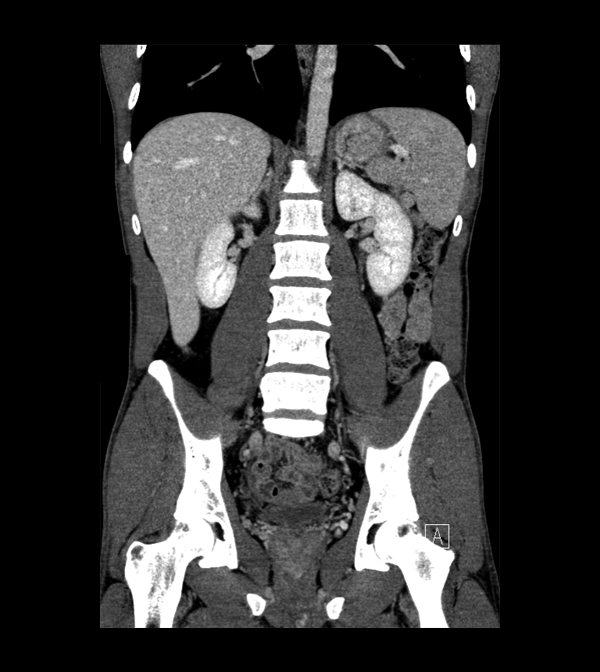

Body

Covers abdominal CT anatomy.